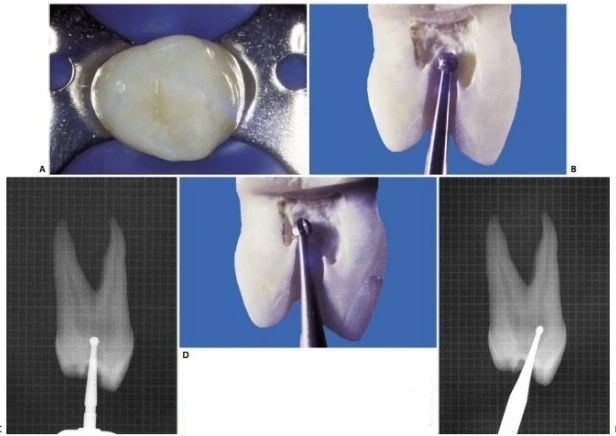

Hình 11.44. A. Mặt nhai của răng cối nhỏ thứ nhất trên. B. Mũi khoan kim cương tròn xuyên qua phần giữa rãnh trung tâm, phá vỡ trần buồng tủy. C. Hình ảnh X-quang. D. Đưa mũi khoan đã dùng trước đó vào lỗ đã được mở ở giai đoạn xuyên qua, trên đường đi ra, chạy mũi khoan để lấy đi những phầncòn lại của trần buồng tủy. E. Hình ảnh X-quang (còn tiếp).

Khi xuyên qua với một mũi khoan kim cương tròn và tay khoan siêu tốc, cần kết hợp chuyển động mũi khoan theo chiều ngoài trong để phát họa đường viền mặt nhai của xoang tủy. Cần ghi nhớ rằng: trong giai đoạn xuyên qua, mũi khoan không nên tạo một xoang tủy dạng ống với các thành song song, mà nên kết hợp với chuyển động xoắn ốc để tạo hình dạng phễu khi khoan xuống lớp ngà. Khi đã xuyên vào đến buồng tủy, sử dụng tay khoan chậm để lấy phần ngà còn lại sau giai đoạn xuyên qua (hình 11.44 D, E).

Dùng mũi khoan đầu trơn với tay khoan siêu tốc tạo hình dáng của xoang mở tủy ở giai đoạn hoàn thành và làm loe (hình 11.44 F,G). Hình dạng của xoang mở tủy khi hoàn thành có hình trứng với đường kính lớn hơn theo chiều ngoài trong và nó thường không liên quan đến đỉnh múi (hình 11.44 H, I). Việc nó có liên quan đến đỉnh múi hay không tùy thuộc vào góc phân kỳ giữa hai chân răng và của hai ống tủy: nếu càng phân kỳ thì xoang tủy càng nhỏ, nếu càng song song thì xoang tủy càng có khả năng phạm đến múi răng. Hai ống tủy thường giao nhau tại một rãnh cạn, ta có thể xác định được rãnh này nếu kiểm tra kỹ sàn buồng tủy (hình 11.45).

. Hình 11.44. (tiếp theo) F. Dùng mũi khoan kim cương ở giai đoạn hoàn thành và làm loe. G. Hình ảnh X-quang của giai đoạn hoàn thành và làm loe. H. Xoang tủy đã hoàn thành. I. Hình ảnh X-quang: múi vẫn còn nguyên.